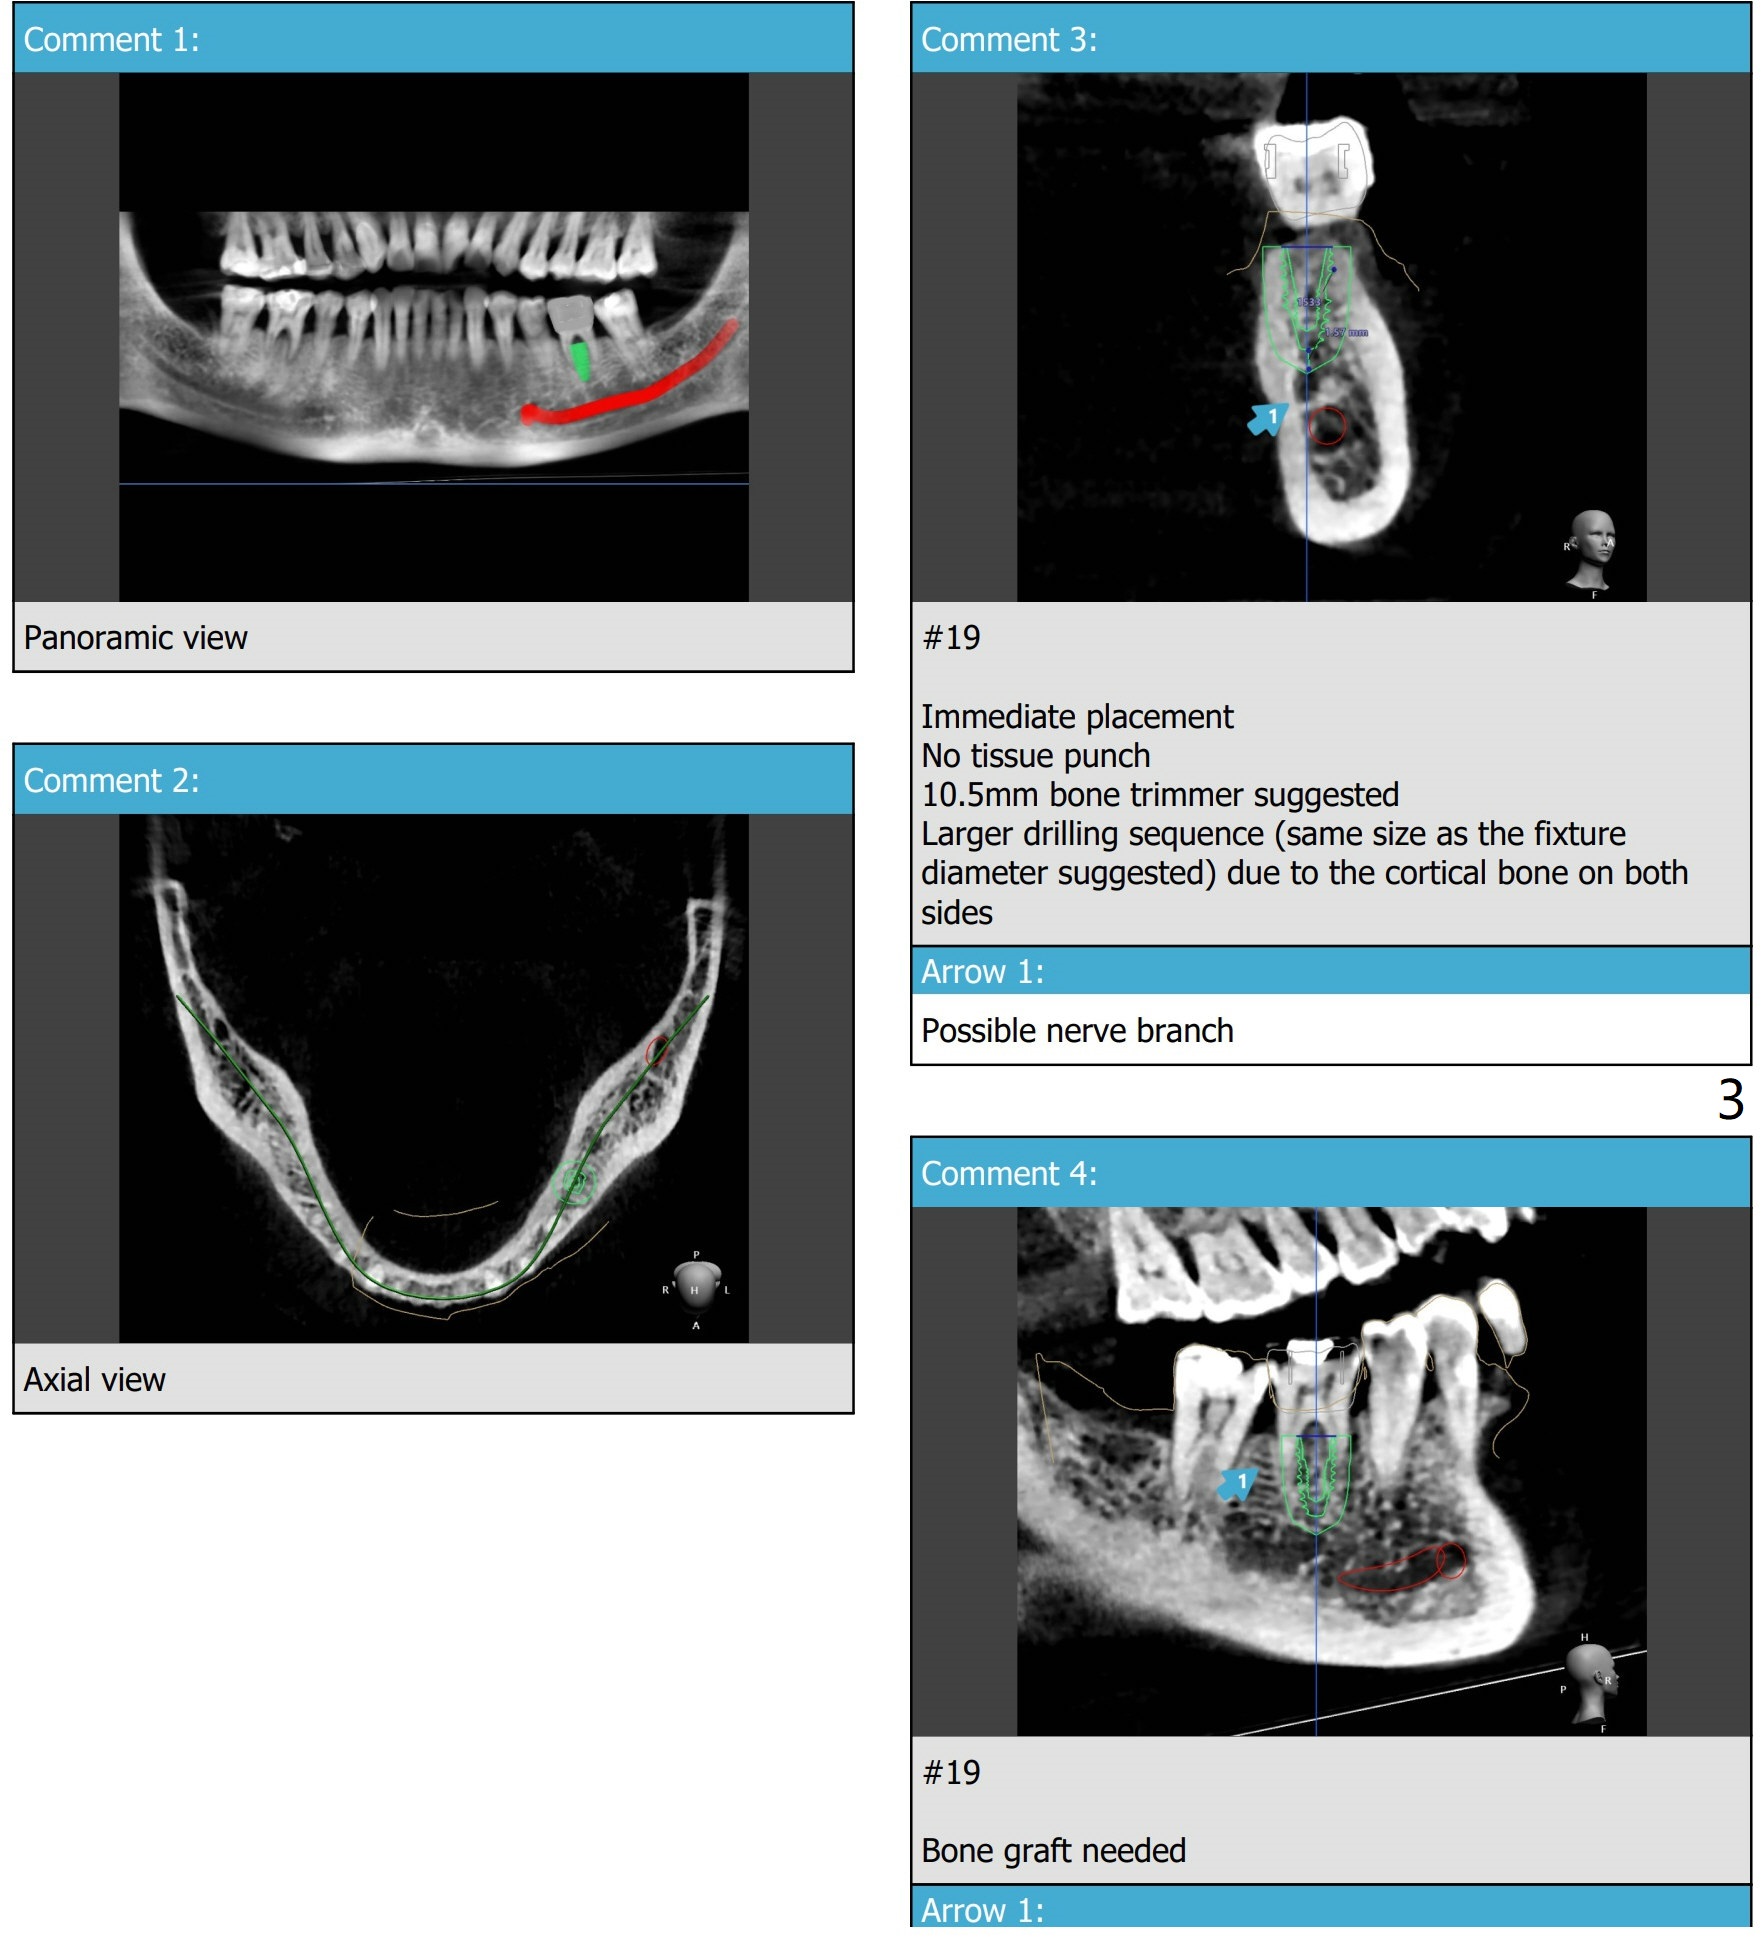

Narrow and Short Implant Due to Accessory Nerve

Remove the tooth (roots), 2.2 mm drill to depth, PA